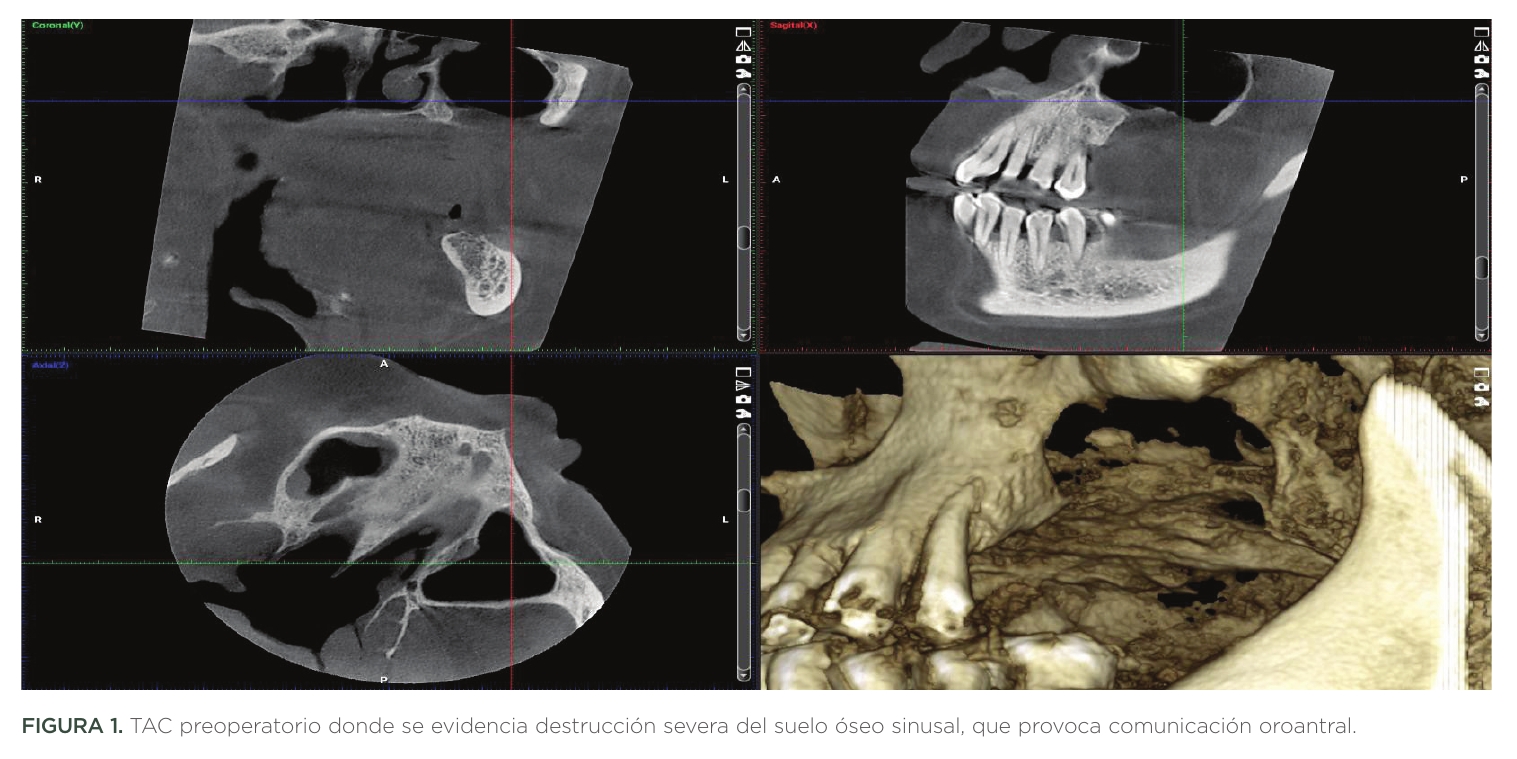

A la exploración se evidenció amplia comunicación OroAntral de 20mm de longitud y 20mm de anchura; además de presencia de pólipos intrasinusales. Además, la patología periodontal estaba presente en todas sus piezas (Figuras 1,2).

Los implantes posteriores fueron insertados en zona 2.8. y 2.8. bis por motivos de baja disponibilidad ósea. En esta zona, el hueso de densidad D4 obligó a la preparación del lecho mediante site formers para aumentar la densidad ósea periimplantaria (Figuras 14,15,16,17).